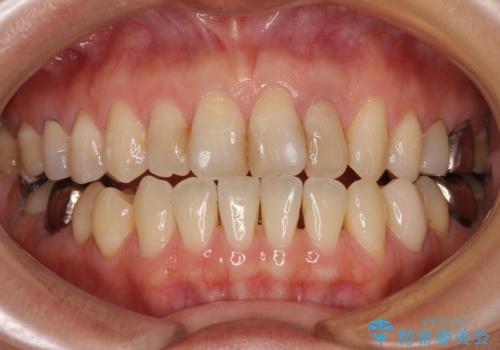

根元がうずく前歯 根管治療とオールセラミック治療

- 前歯に痛みを感じて来院された患者様です。

以前虫歯治療を行った歯が痛み出し、鼻の下を押すと強い痛みを感じていました。

レントゲン写真から、大きくなった根尖病変が認められました。

根管治療を行い、その後オールセラミッククラウンにて補綴治療を行うこととしました。

根管治療後速やかに痛みが消退し、6ヶ月後のレントゲン写真では、根尖部の病変がほぼなくなっていることが分かりました。